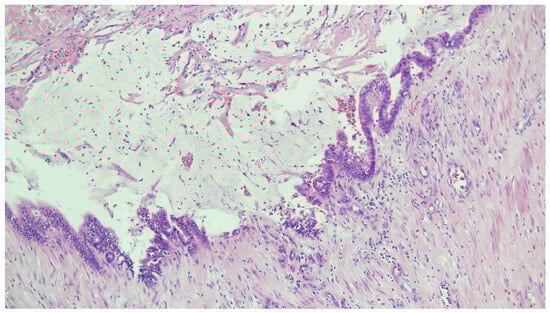

Figure 4.

Histopathology with H&E staining: appendiceal tumor with abundant dissecting mucin pools and residual lining epithelium resting on the subjacent fibrous stroma. Columnar epithelium with low-grade atypia and variable apical mucinous cytoplasm was demonstrated.

Pathology revealed an inverted appendix with a dilated lumen filled with acellular mucin, accompanied by flattened and undulating columnar epithelium with low-grade mucinous cytoplasm (Figure 4). The mucin dissected into the subserosa and involved the adjacent cecum. High-grade cytologic atypia and infiltrative growth were not identified. Ileocecal intussusception due to low-grade appendiceal mucinous neoplasm (LAMN), classified as pT3 disease, was diagnosed.